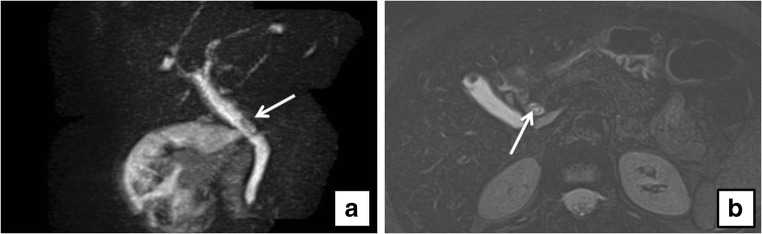

On preoperative US examination, 5 out of 104 patients demonstrated a dilated CBD and, among them, only one patient (20%) presented CBD lithiasis on MRCP, whereas 6 out of 99 patients (6%) with normal choledocal diameter showed CBD lithiasis (Figs. 1, 2, 3, and 4).